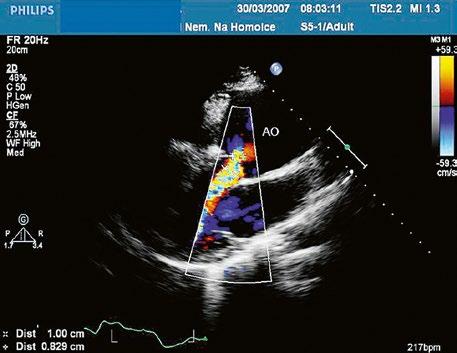

Obr. 45.24 TTE, parasternální dlouhá osa, těsně pod aortální chlopní (AO) je patrná diskontinuita v oblasti membranózního septa (šipka) s levopravým zkratem mezi levou komorou a pravou komorou LK – levá komora, LS – levá síň, PK – pravá komora

Obr. 45.25 V TEE je vidět menší perimembranózní defekt (šipka) s levopravým zkratem těsně pod aortální chlopní (AO). Šíře barevného jetu nadhodnocuje vlastní šíři defektu. PK – pravá komora

Poslechově má malý VSD typický hlučný systolický šelest vlevo parasternálně ve 3.–4. mezižebří. Velký nerestriktivní VSD s plicní hypertenzí nemívá tento typický šelest, ale pouze akcentaci 2. ozvy nad plicnicí. Echokardiografie je hlavní diagnostickou metodou (Obr. 45.24−45.35, Video 45.22−45.36).